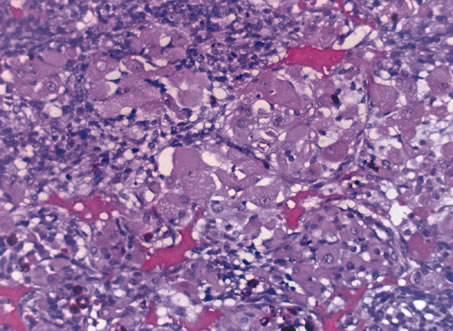

In 1931, Callender classified uveal melanomas based on cytologic features.166 He described six groups, four of which were based on cytology and two on other histologic features. The groups based on cytology were tumors composed of (1) spindle-A cells, (2) spindle-B cells (Fig. 26), (3) epithelioid cells (Fig. 27), (4) a mixture of epithelioid and spindle cells (Fig. 28). The fifth group consisted of tumors with a fascicular pattern, and the the sixth group was composed of tumors that could not be classified in the other groups because of extensive necrosis (Fig. 29). Spindle cells are described as fusiform and arranged in tightly cohesive bundles. The plasma membranes of the cells are indistinct and have a syncytial appearance. Spindle-A cells have a slender nucleus with fine chromatin and a longitudinal fold in the nuclear envelope that gives the appearance of a line. Spindle-B cells have a slightly plumper nucleus, coarser chromatin, and a more prominent and eosinophillic nucleolus. Epithelioid cells are larger and more pleomorphic. They have an abundant glassy cytoplasm, a polyhedral shape, and a distinct cell border and are less cohesive. Epothelioid cells tend to have a larger and rounder nucleus than the other types, with a more angular nuclear envelope and irregular indentations. The chromatin is coarse and marginated, and large eosinophillic nucleoli are present.

Fig. 26. Choroidal melanoma. Note spindle-B melanoma cells with nucleoli. (Hemotoxylin-eosin ×160.)

Fig. 27. Choroidal melanoma. The epithelioid melanoma cells show large nuclei and prominent nucleoli. (Hemotoxylin-eosin ×160.)

Fig. 28. Choroidal melanoma. The tumor shows a mixture of spindle cells and epithelioid cells. Both spindle A and spindle B cells are present. (Hemotoxylin-eosin ×160.)

Fig. 29. Choroidal melanoma. Necrotic tumor cells are mixed with melanophages. (Hemotoxylin-eosin ×200.)